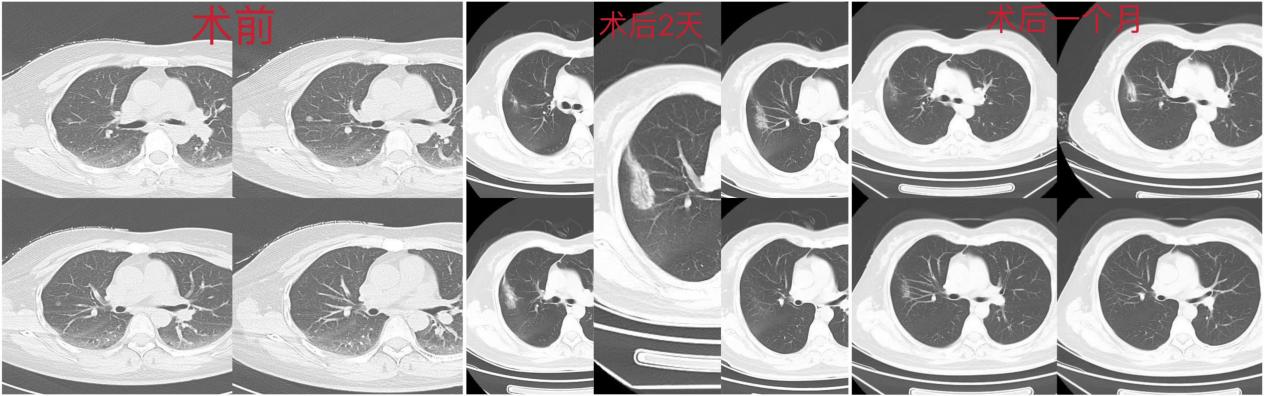

患者巍某,40岁,3年前体检胸部CT提示右肺下叶磨玻璃结节,大小约8X7mm,期间一直服用中药。今年6月复查,发现磨玻璃结节实性成分增加,影像提示高危结节。由于热爱自己的职业,拒绝手术治疗,思虑忧重,万全考虑之下科室决定为其行肺部结节微波消融微创术。该技术创伤小、精准适形、疗效明确、操作相对简单、安全性高、恢复迅速,对无法肺部手术的巍某带来新的希望。手术在北京大学肿瘤医院介入科柳晨教授、我院CT科阚庆玲主任的指导下,由主治医师闫强消融团队为巍某实施肺结节微波消融术超微创精准治疗。

为让患者尽快康复,呼吸与危重症医学科何佳木、赵翠翠医护团队单独为患者划分了病区。经数日精心护理下,患者恢复良好,现已顺利出院。术后1月患者复查CT,消融范围覆盖原结节,原结节未显示,消融范围良好,病灶凝固坏死良好,无远期并发症。患者工作、生活如常。